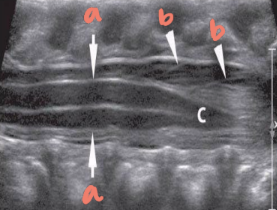

a

right

b

posterior

c

left

d

anterior

solid white arrow

echogenic epidural fat

vb

vertebral bodies

intervertebral disks

p

spinous processes

arrowheads

arachnoid/dural layer

e

epidural space

*

subarachnoid space w/ CSF

sc

hypoechoic spinal cord